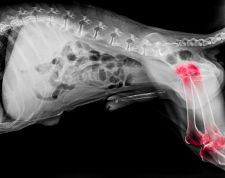

HD bei Hunden – was tun?

Als HD wird die Hüftgelenksdysplasie bezeichnet. Diese Krankheit tritt leider bei Hunden sehr häufig auf. Sie betrifft v.a. grössere Rassen, kann aber auch Vertreter kleinerer Rassen betreffen. Es ist aufgrund der ähnlichen Symptome nicht immer einfach, die HD von der Arthrose zu unterscheiden. Wir erklären hier, was die HD genau ist und was wirklich helfen kann.